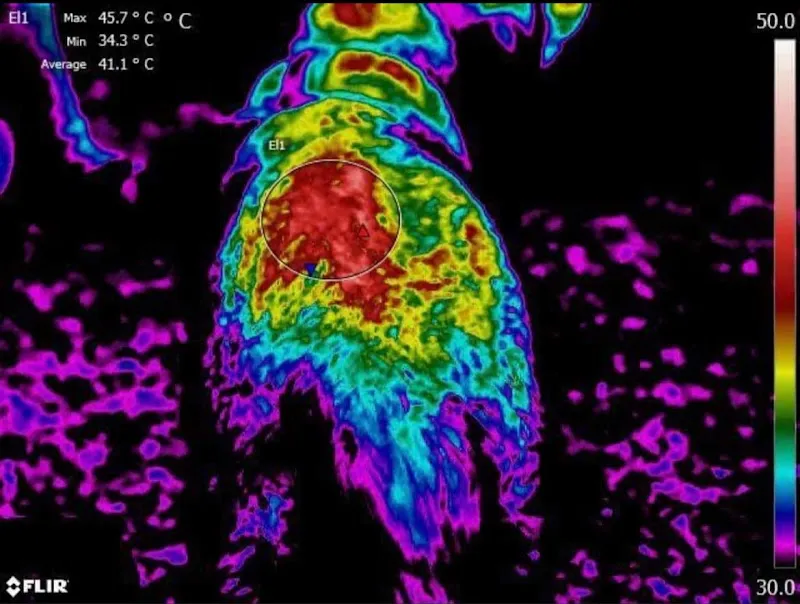

📍 Hägliloo 237, 8222 BeringenTierheilpraxis für alternative Tiermedizin - Nadia Knöpfel ist ein Tierarzt in Beringen, Kanton Schaffhausen. Dein Schlüssel zum gesunden Tier Mein Motto: «Aufgeben ist keine Option, für jedes Problem gibt es eine Lösung!» Meine Tierheilpraxis ist oft die letzte Anlaufstelle, wenn alles andere bereits versucht wurde und hoffnungslos scheint. Doch ich kann dir versprechen, für jedes Problem gibt es eine Lösung, man muss sie nur finden! Ich stehe dir und deinem Tier zur Seite, du darfst mich immer und zu jederzeit kontaktieren. Als Tierheilpraktikerin betrachte ich das Tier ganzheitlich. Die Krankheit steht bei mir nicht im Vordergrund, sondern der Ursprung, der die Krankheit auslöst. Hier spielen viele Faktoren zusammen, die Psyche, das Umfeld, die Fütterung, die Haltung auf all diese Faktoren lege ich meinen Fokus. Voraussetzung für einen Erfolg ist Geduld und eine gute, enge Zusammenarbeit, denn niemand kennt sein Tier besser als du selbst. Ich bin für dich und dein Tier da, zögere nicht mich zu kontaktieren, gemeinsam sind wir stark und schaffen Unmögliches. © 2025 HORSETHERAPIE Bewertet mit 5.0 von 5 Sternen (1 Bewertungen).